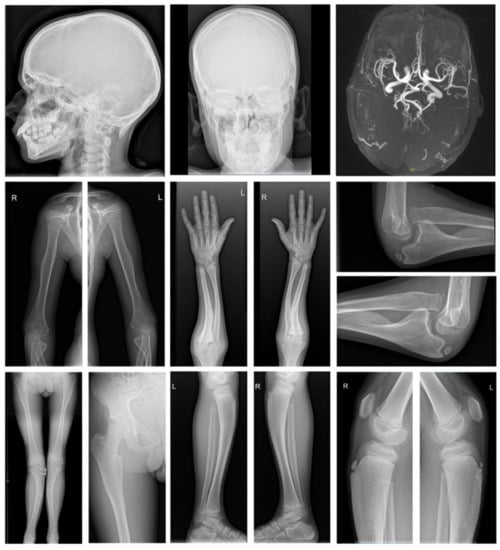

3.1. Clinical Characteristics